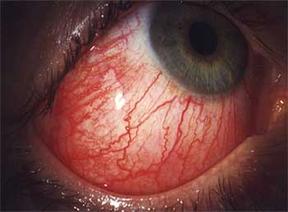

Die Bindehautentzündung

Die

Bindehautentzündung oder „Konjunktivus“ ist die

häufigste Erkrankung des Auges überhaupt. Sie kann durch von außen kommende

oder – viel seltene – von innen stammende Reize entstehen.

Die Ursachen können allergische Reaktionen wie bei Heuschnupfen, Entzündungen durch Fremdkörper, Augentrockenheit, reizende Substanzen, die ins Auge gelangen, oder übertragbare Formen, die durch Bakterien und Viren ausgelöst werden, sein. Manchmal ist die Bindehautentzündung auch Symptom einer zugrund liegenden rheumatischen Erkrankung.

Die Symptome der Bindehautentzündung sind ein „rotes Auge“, Fremdkörpergefühl, Jucken, Brennen und verstärkte Sekretion mit Verkleben der Augenlider am Morgen. Lichtempfindlichkeit und stärkere Schmerzen deuten auf die Beteiligung der Hornhaut hin.

Abb. 1: Das stark gerötete Auge bei einer

Bindehautentzündung (aus: siehe Literaturverzeichnis)

Abb. 2 (aus: siehe Literaturverzeichnis)

Die Lage der Bindehaut macht sie besonders empfänglich für Reize und Keime von außen. Für Keime ist sie die Eintrittspforte in den Körper.

Die Bindehaut wird meistens als eine milde Erkrankung gesehen, da die Blutversorgung, die hohe Reaktionsfähigkeit auf Entzündungen, der reiche Besatz an immunkompetenten Zellen und die Abwehrenzyme der Tränenflüssigkeit die wichtigsten Vermittler einer guten Abwehrfunktion sind. Doch es können auch schwere Formen auftreten, die das gesamte Auge und damit das Sehvermögen bedrohen.

Die Bindehautentzündung wird je nach Ursache mit antibiotischen, antiallergischen, kortisonhaltigen oder wirkstoffreichen Augentropfen behandelt.